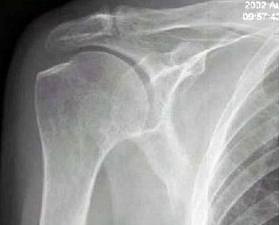

右肩关节活动不便1年多,体检发现右手上抬不能,后展受限,行右肩关节摄片如图示,最好的诊断是()

A:正常右肩关节

B:右肱骨骨质疏松

C:右肩关节周围炎

D:右肩关节滑囊炎

E:以上都不是